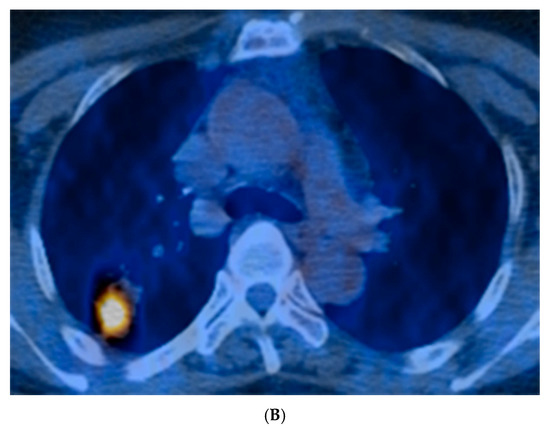

| 18FDG-PET/CT (n = 41) | |

| SUVmax | 4.9 (2.5–8.7) |

| SUVmax (>2.5) | 31/41 (76) |